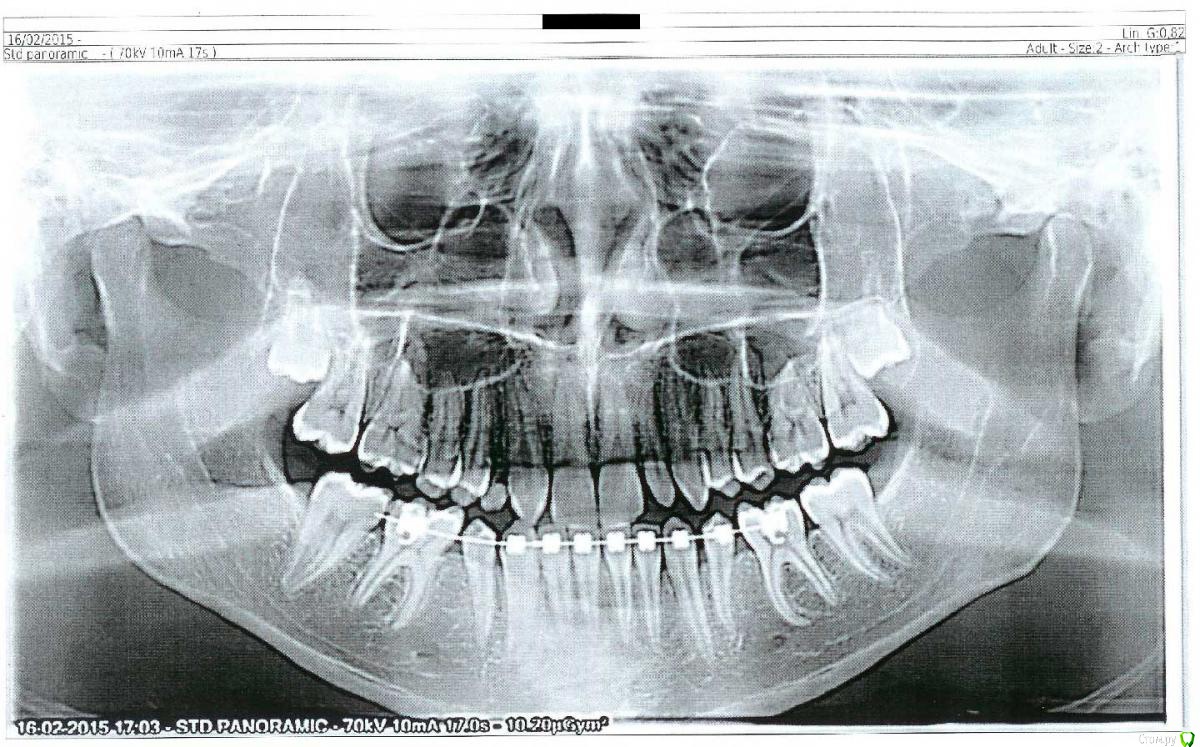

Сейчас мне 17 лет. На лечении у ортодонта с августа 2013 года. Удалили молочные пятерки и стали сдвигать шестерки к передним зубам. На верхнюю челюсть она ставить брекеты не стала. Осенью 14 года врач ушла в декрет.

Пришел новый врач который предложил все сделать несколько иначе: поставить брекеты на обе челюсти, все выравнять и освободить место под будущие импланты: вместо пятерок снизу и второго слева резца сверху -, а пока на их место поставить коронки. Также врач назвал сроки: около 1 года.

Сверху слева отсутствует зачаток второго резца, вместо него находится клык и молочный зуб левее. Внизу нет зачатков пятерок.

доктор ваш мыслит верно - однаконадо рещить вопрос и с прикусом - нужно трг , кт суставов с сомкнутыми зубами .а просто кт . модели в артикуляторе - полный анализ.